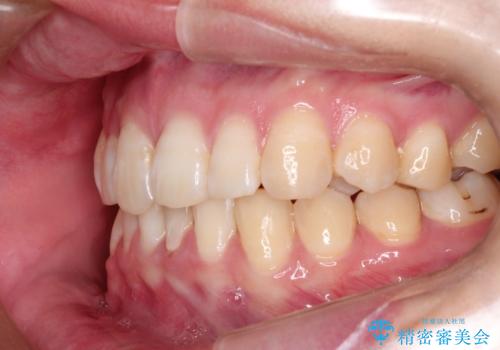

ハーフリンガル ワイヤー矯正による非抜歯・過蓋咬合の治療

- 非抜歯、大臼歯遠心移動による臼歯関係の是正・過蓋の改善をハーフリンガル・ワイヤー矯正にて計画した。